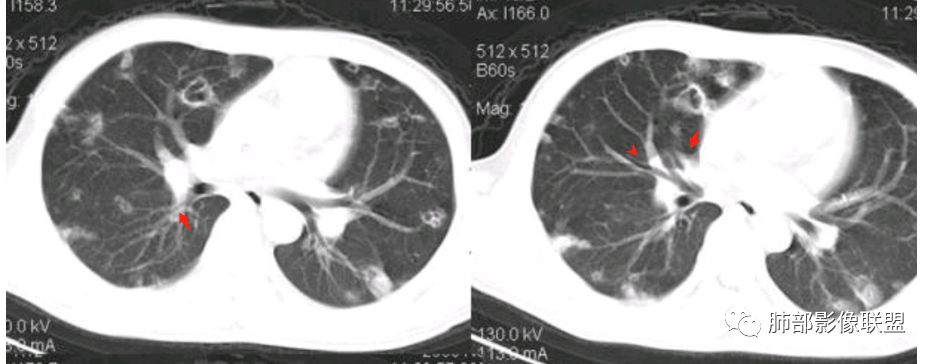

南边:青年男性,急性起病,多发结节或囊腔——胸膜下分布结节,与支气管关系不密切,支气管壁不增厚,首选血道来源,不是气道来源

南边:

血道来源的:

1、感染性:金葡菌?克雷白杆菌?曲霉菌?

2、血管炎性:血管炎?

3、肿瘤:血管肉瘤?转移瘤?

结果

(血源性)金葡菌肺炎(血培养金黄色葡萄菌)

金黄色葡萄球菌:革兰阳性菌,涂片表现为成对的短链状四联球菌或簇状。金葡菌肺炎:是由金黄色葡萄球菌引起的急性化脓性肺部感染,常发生于免疫功能受损的病人。主要分为原发性(吸入性)金葡菌肺炎和继发性(血源性)金葡菌肺炎。血源性金葡菌肺炎:常继发于金葡菌败血症及脓毒血症,由细菌栓子经血液循环至肺而引起。多表现为肺外周和基底部分布为主的多发点片状影或类圆形结节影。菌栓引起多发性肺小动脉栓塞,导致双肺多发性化脓性炎症,进而组织坏死形成多发性肺脓肿,并可累及胸膜产生脓胸或脓气胸。诊断要点:    1.金黄色葡萄球菌引起3%的社区获得性肺炎及15%的  医院获得性肺炎    2.金黄色葡萄球菌肺炎的主要危险因素是静脉输液和ICU患者。    3.常见的影像学表现:    1)单侧(60%)或双侧(40%)斑片状实变影(支气管肺炎)    2)空洞性结节(直径4~10mm)

1.金黄色葡萄球菌肺炎是典型的肺部化脓性感染之一。临床中毒症状明显,常寒颤高热起病,脓性痰、血丝痰等。

换句话说,一般情况较好,慢性起病,症状轻微的一般不会是它。

2.常有临床线索,皮肤脓肿、伤口感染、蜂窝织炎、化脓性骨髓炎、严重病毒感染后等等。

3.病情变化快,影像进展迅速,尤其是血播患者。易形成脓肿。

4.影像典型血行播散的特点,脓毒栓子,结节影,片影等。

5.短期内(如一两天内)迅速出现的有张力的菲薄气囊影,或多发成串成簇分布的,尤具特征性!这也明显有别于肺炎克雷伯杆菌肺炎及曲霉病。

如病灶迁延,厚壁脓肿,则影像上与后者不易区分。